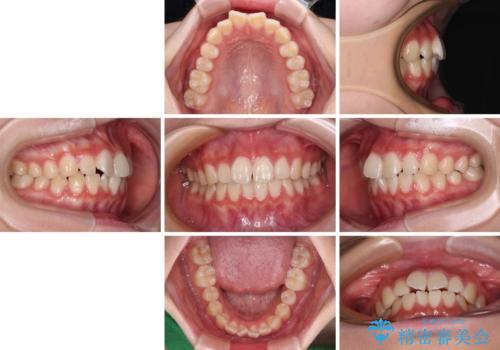

- 上下前歯のねじれを気にして来院された患者様です。

ワイヤー矯正でもマウスピース矯正でも対応可能でしたが、マウスピース矯正の自己管理が面倒であること、上顎前歯の捻転が著しいことから、ワイヤー矯正での治療を希望されました。